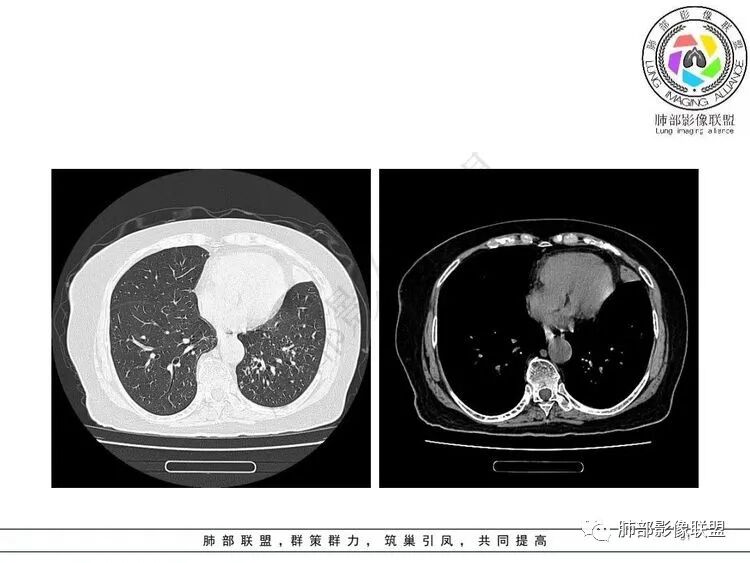

左肺上叶大片状实变,边缘部分清晰,密度不均,支气管部分扩张扭曲,同时散在分布小透光区,左下肺沿肺段及纹理走形斑点,粟粒影及树芽征。考虑左肺感染性病变,结核首选,其它感染待排

女,65胸闷,气促半月入院,左肺上叶见大片状实变影,边缘模糊,其内见含气支气管征,支气管管壁不规整,凹凸不平,广泛性狭窄、僵硬、扭曲,左肺下叶另见粟粒,结节及树芽征征,结核感染T细胞阳性,考虑结核可能,除外其它感染性病变。

老年女性,糖尿病,不发热,影像左肺上叶大片状实变,边缘部分清晰,密度不均,支气管部分扩张扭曲,左肺下叶可见粟粒影及树芽征。考虑左肺感染性病变,首先结可能性大核,NTM待排除。

老年女性,有糖尿病病史。边缘模糊不清,左肺上叶大片状实变密度影,内可见支气管穿行,走形迂曲并扩张,另左肺下叶多发点状高密度影,并树芽征,考虑结核

3.左肺上叶较大范围实性密度区,密度偏高不均,支气管穿行且轻度扩张,可见无壁不规则空洞(未能显示外壁),未显示液平或腔内结节。

4.左肺下叶多发结节影及条索影,密度不均,边界较清楚,可见树芽征。

1.左肺上叶较大范围实性密度区,支气管未见阻塞,无壁空洞,整体比较“干”,加之纵隔左移,比较符合病程较长的结核性病变。

左肺下叶多发结节影、条索影、树芽征等具有相当明显的提示意义—符合继发性肺结核。